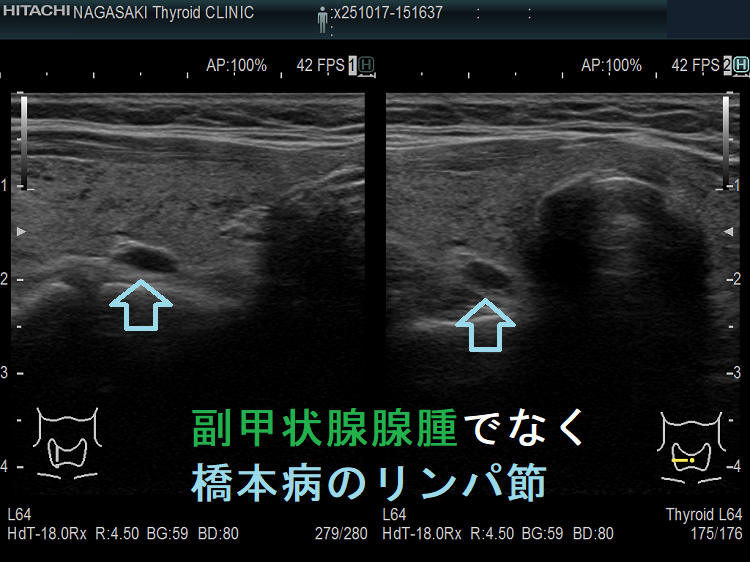

- 実はただのリンパ節、頚部異所性甲状腺、排液後縮小した甲状腺のう胞腺腫(甲状腺嚢胞腺腫)、甲状腺腺腫様結節

副甲状腺腺腫のように見えるも、実はただのリンパ節

副甲状腺腺腫との違いとして、リンパ節では

- 内部血流が無く

- リンパ門が存在します(ここだけ血流があります)

ケース③